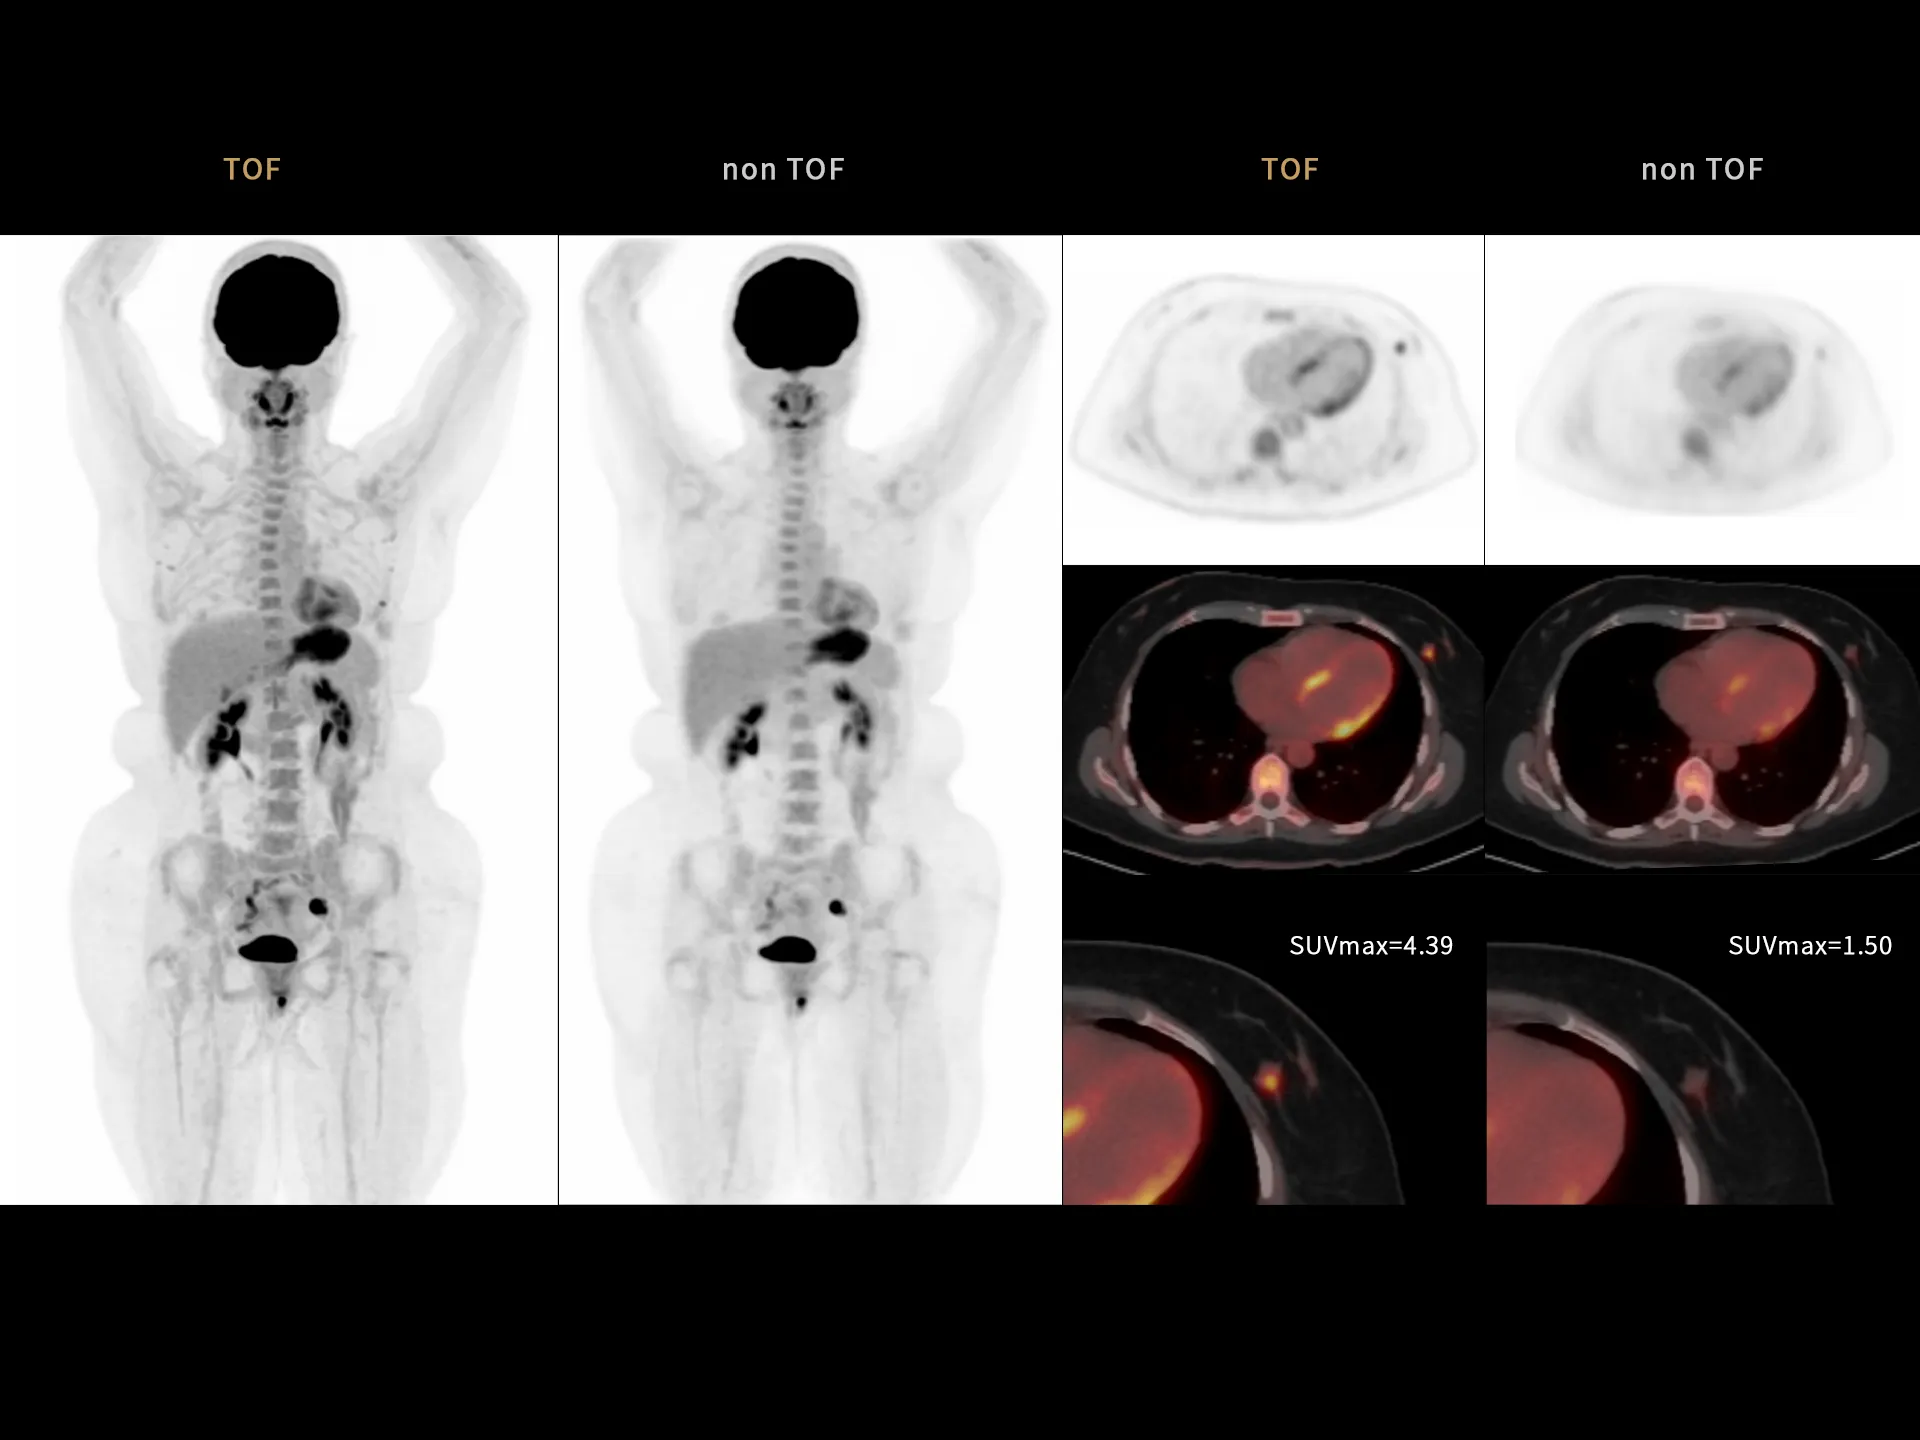

219 ps

Leading TOF resolution that boosts small lesion detectability and clarity.

High effective sensitivity that benefits from TOF gain leverages better diagnostic accuracy under low dose usage and fast scan time.